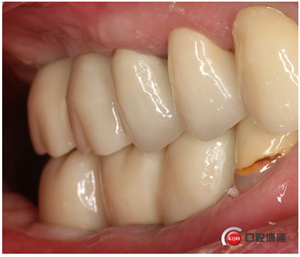

試戴冠,看起來還不錯哈,但我不滿意,大家看看有什么問題?看看下頜那幾顆比較明顯。

問題在這里,不給留位置怎么會有齦乳頭,沒有間隙怎么清潔?這完全是技工的錯吧?算了我自己修整一下吧。

再看看是不是效果好多了?哼!我就是個較真兒的人。